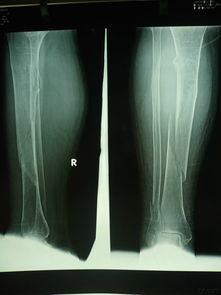

由于腓骨并不是主要的人體承重骨,所以當劇烈的運動之后或者是突然遭受了過大的外力撞擊都是會直接導致腓骨骨折的,所以在平時運動的時候要注意,一定不要受到撞擊或者是運動程度過于激烈,運動最好是要以安全為主。